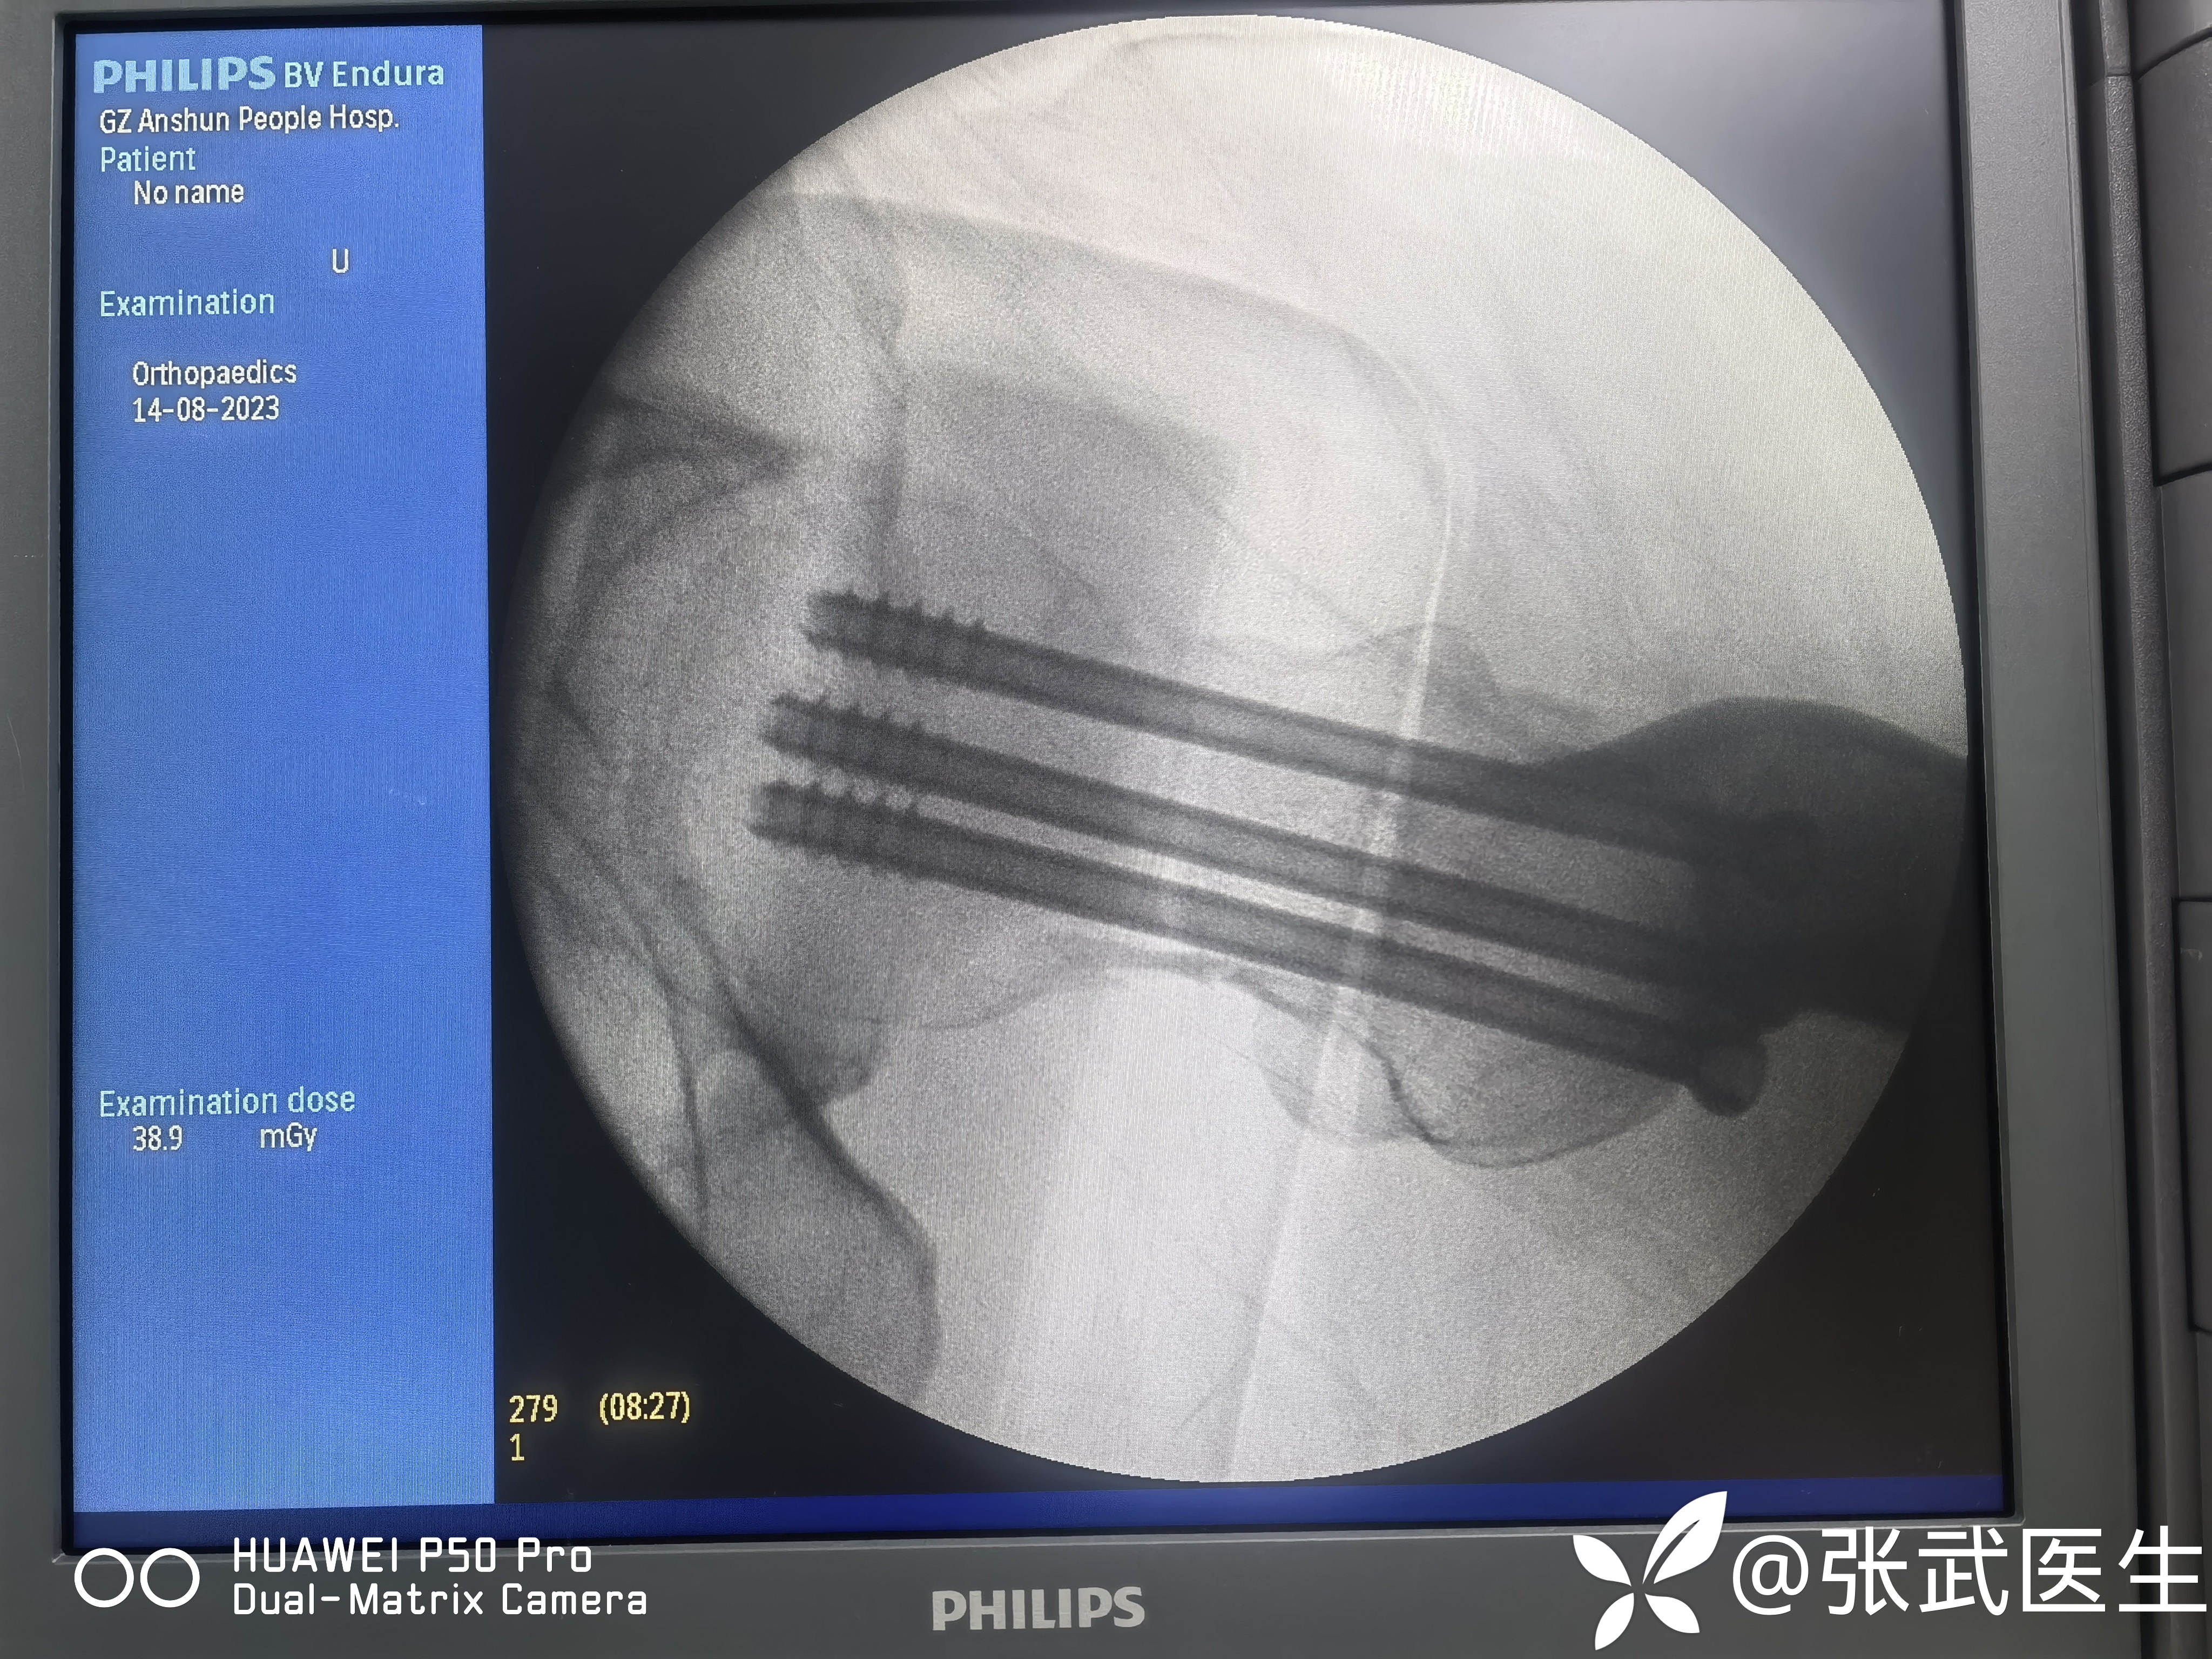

克氏针置入情况

先置入股骨距克氏针,以此为参照物置入另两枚,呈倒三角。

分别置入7.3mm*95mm 7.3mm*90mm 7.3mm*90mm三枚

置钉呈平行,分散,靠边。